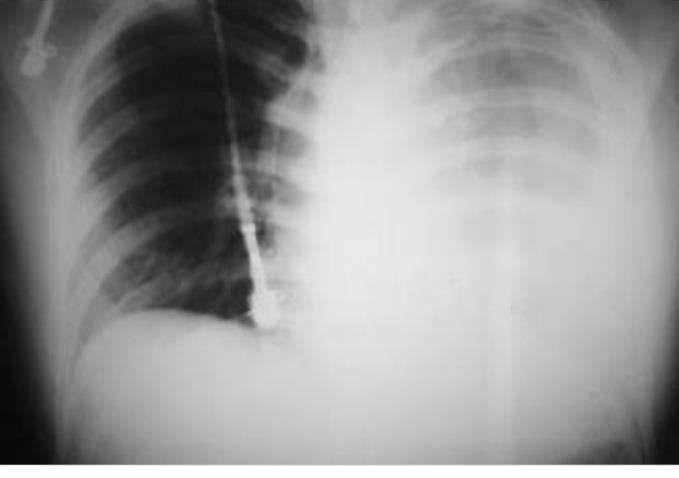

Прислушиваясь к себе в течение десяти минут уже дома, прихожу к выводу: отломок седьмого правого ребра в плевральную полость и лёгочную ткань как минимум уткнулся. Точнее сказать не могу: больно. Очень больно.

Опять же, по тем же личным ощущениям, очень похоже на начинающийся отёк. Плюс видимая гематома в месте сломанного ребра, б**…

Через некоторое время начинается одышка. Гемоторакс?⁴

⁴Скопление крови в плевральной полости. Является следствием кровотечения из сосудов лёгких, внутригрудных ветвей крупных сосудов (аорта, полые вены), грудной стенки, средостения, сердца или диафрагмы.

А вот тут — жёсткое нет. Не нужно мне обследоваться. Потому что зашивать нужно по-любому, плюс скобы на рёбра. И если рукастого хирурга с минимальным набором опыта и инструментов представить ещё можно, то тот же рентген — это уже дополнительное звено. Лишнее.

Попутно: хорошо если рентген и хирург находятся за общей дверью. А если рентген в одном конце города, хирург в другом? Ну а чё, с учётом местного подхода, вполне реальная перспектива. Печально, но с местного рентгена до хирурга можно и не успеть добраться. Интересно, а пробки у этих летучих авто бывают?

Если мыслить логически, хирург без рентгена — это решение. Для меня лично, сейчас, идеальное практически. Хирург и разрежет, и посмотрит, и устранит.

А вот рентген — всего лишь один из возможных инструментов диагностики. Даже если последнюю исполнить на десять баллов из десяти, моей проблемы это не решает. Лишь уточняет масштаб, что есть абсолютно паразитный и ненужный этап.